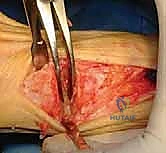

الخطوة 1: التعامل مع الشق الجراحي القديم وإزالة المعادن

- يبدأ الدكتور هطيف بفتح الجلد، غالبًا باستخدام الشق الجراحي القديم لتقليل الندبات، مع استئصال الأنسجة المتندبة (Scar excision) بحذر شديد لحماية الأعصاب والأوعية الدموية.

- يتم تحديد مواقع المسامير أو الشرائح المعدنية من الجراحة السابقة وإزالتها (Hardware Removal). قد تكون هذه الخطوة صعبة إذا نما العظم فوق المسامير.

الخطوة 2: إعادة تقييم الأنسجة الرخوة (Soft Tissue Balancing)

- يتم فحص العضلة المقربة (Adductor Hallucis). إذا كانت مشدودة وتسبب انحراف الإصبع، يقوم الدكتور هطيف بتحريرها بدقة متناهية (Lateral Release).

- يتم تحرير محفظة المفصل المنكمشة لتسمح للإصبع بالعودة إلى وضعه المستقيم.

الخطوة 4: الإغلاق التجميلي

لأن القدم عانت من تدخلات جراحية متعددة، يستخدم الدكتور هطيف تقنيات الجراحة التجميلية الدقيقة في خياطة الجلد لتقليل التندب وتسريع التئام الجرح.